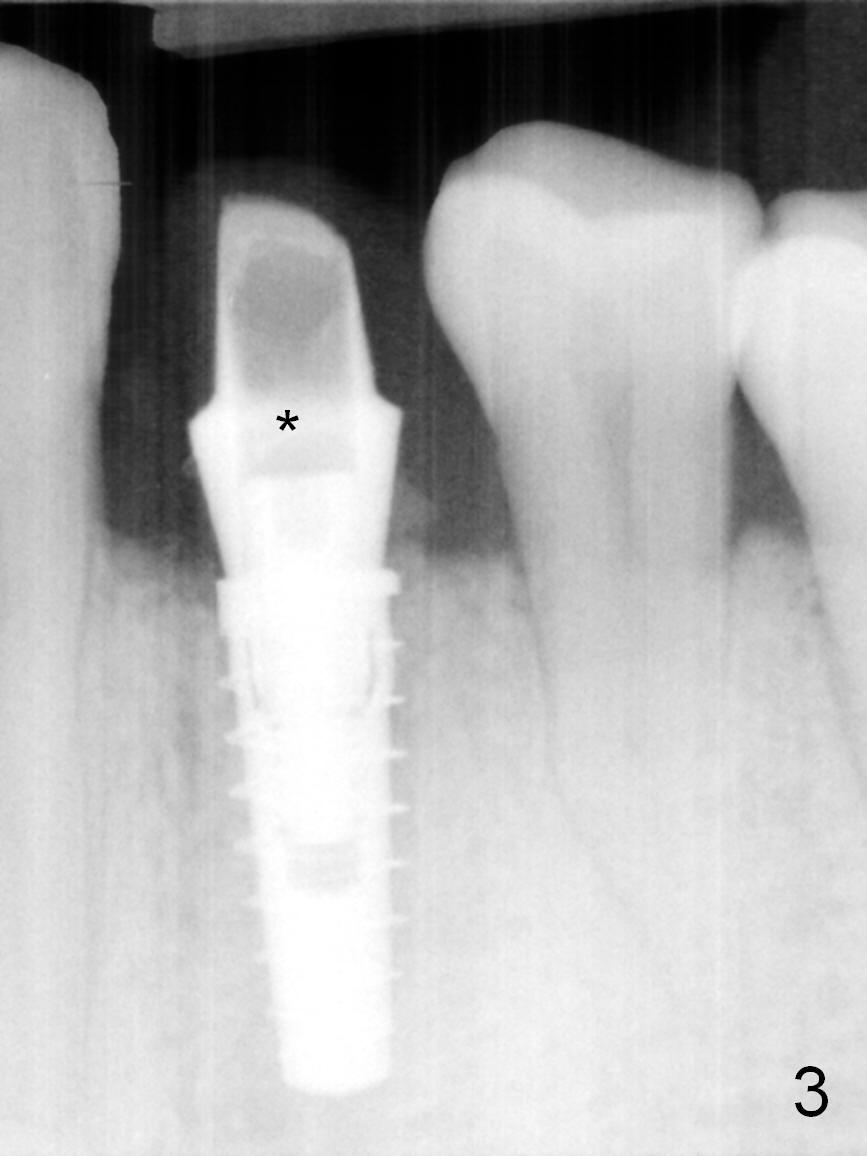

The residual root at #21 seems to be buccally positioned (Fig.1 *). The initial osteotomy is established with the 1.6 mm drill at 11 mm (Fig.2). Later the depth increases to 13 mm. The initial osteotomy is found to be too lingual, but experience shows that as osteotomy increases in diameter, the trajectory would shift buccally due to the thick lingual plate (slope). When 3.3 mm Magic drill reaches 11 mm, the patient feels pain. It is probably due to the dense bone. A 4x11 mm IBS implant cannot be seated due to high torque; it is removed. The osteotomy is increased with 3.8 mm drill. The implant is re-seated with >55 Ncm; it is over-lingually placed. Due to failure to seat the implant driver completely, the implant cannot be un-torqued. A 4.5 mm 15° angled abutment (3 mm cuff) is placed for immediate provisional (Fig.3,4 *).

The implant seems to have osteointegrated 4 months postop (Fig.9). When a permanent crown is fabricated, it should have normal occlusal and buccal contour (from Fig.11 (provisional) to 12 red and black curved lines) as well as the buccal cervical extension (Fig.12 to cover the buccal gingiva (Fig.10 *). If the lingual margin of the abutment is too prominent, return the case and the abutment will be changed to the one with 2 mm cuff (existing 3 mm). The lingual margin of the abutment will be trimmed. The patient is not pleased with the short buccal margin of the crown after cementation (Fig.13). In fact the provisional should have been fabricated so that the its buccal margin should be subgingival and within the gingival outline. It may prevent buccal plate collapse. In fact the crown dislodges 1 year post cementation. The lingual margin is prep lower to increase the abutment height. Impression is taken. Although the access hole is unnecessary for cementation, it acts as an escape hole so that there is no excess cement cervically (Fig.14-18).